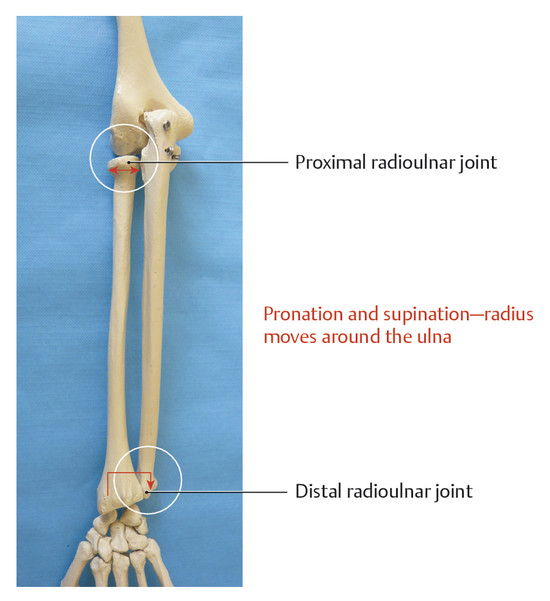

RADIO CUBITAL PROXIMAL Y DISTAL

movimientos